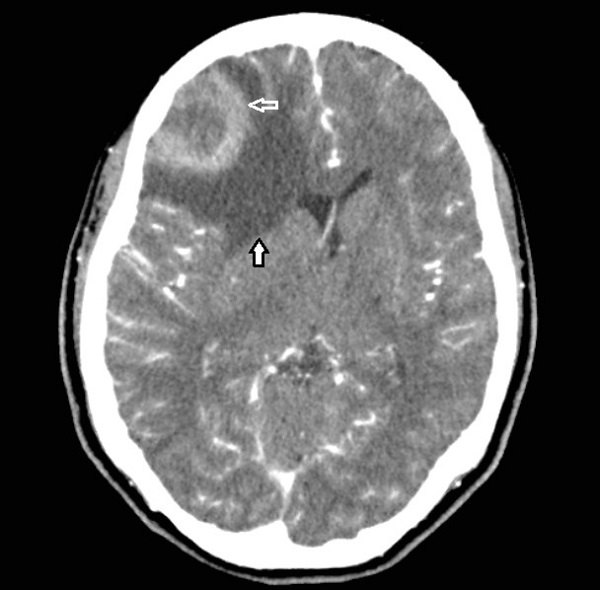

En la TC y RM las metástasis cerebrales se clasifican según el número de lesiones en: i) únicas, ii) oligometástasis (una y tres lesiones) iii) y múltiples (más de tres lesiones)28; estas producen efecto masa con desplazamiento de estructuras vecinas afectando espacios subaracnoideos o ventriculares, dependiendo la ubicación12; se localizan en la unión entre la sustancia gris y blanca, y con contraste, se produce intensificación de los bordes de la lesión, en forma de anillo (Figura 2)28.

La RM tiene mayor sensibilidad y especificidad51, pero en ambos métodos se observan tres patrones característicos: necrosis, hemorragia y neovascularización. Se observa masa única con necrosis central, intensificación en anillo (células con alta actividad proliferativa) y un área peritumoral extensa de edema vasogénico (Figura 2).

En la RM se observan hipointensidad en T1 e hiperintensidad en T2. Puede presentar diseminación bihemisférica a través del cuerpo calloso, con afección de lóbulos frontales (Glioma en “alas de mariposa”)50,52.